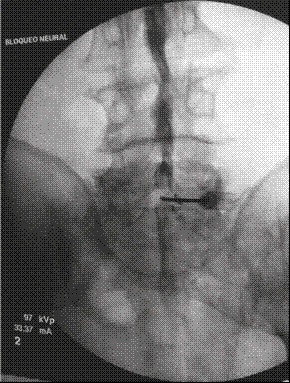

Previas asepsia y antisepsia en la zona lumbar e infiltración de la piel y el tejido celular subcutáneo con 3 mL de lidocaína simple al 2 % al nivel L5-S1, se avanzó una aguja Touhy n.º 17, se obtuvo pérdida de la resistencia al aire y se intentó acceder al espacio epidural L5-S1 (Figura 1). Se inyectó 1 mL de contraste no iónico (Omnipaque™ 300) y se obtuvieron luego imágenes fluoroscópicas del canal espinal lumbar en proyecciones AP y lateral (Figuras 1 y 2), en las que no se detectó anticipadamente un patrón subdural de la inyección por lo que se asumió la inyección epidural interlaminar L5-S1. Se procedió a inyectar en dicho nivel 10 mL de un preparado consistente en 80 mg de metilprednisolona más 10 mg de bupivacaína simple al 0,1 %, se retiró la aguja intacta y se trasladó al paciente a la sala de recuperación, con signos vitales estables, consciente y cooperando al cambio de posición hacia la camilla de transporte.

El diagnóstico de certeza del bloqueo subdural es radiológico 20. En el primer caso, guiado por fluoroscopia, se pudo observar, luego de la aplicación del medio de contraste, la distribución subdural en la proyección AP, como una extensa dispersión a varios niveles por encima y por debajo del sitio de inyección, con patrón homogéneo del contraste (Figura 1). En la proyección lateral (Figura 2) se observó una colección densa de medio de contraste con abombamiento a la porción central del canal espinal, que no salía a las raíces espinales laterales o a la porción inferior del saco tecal.